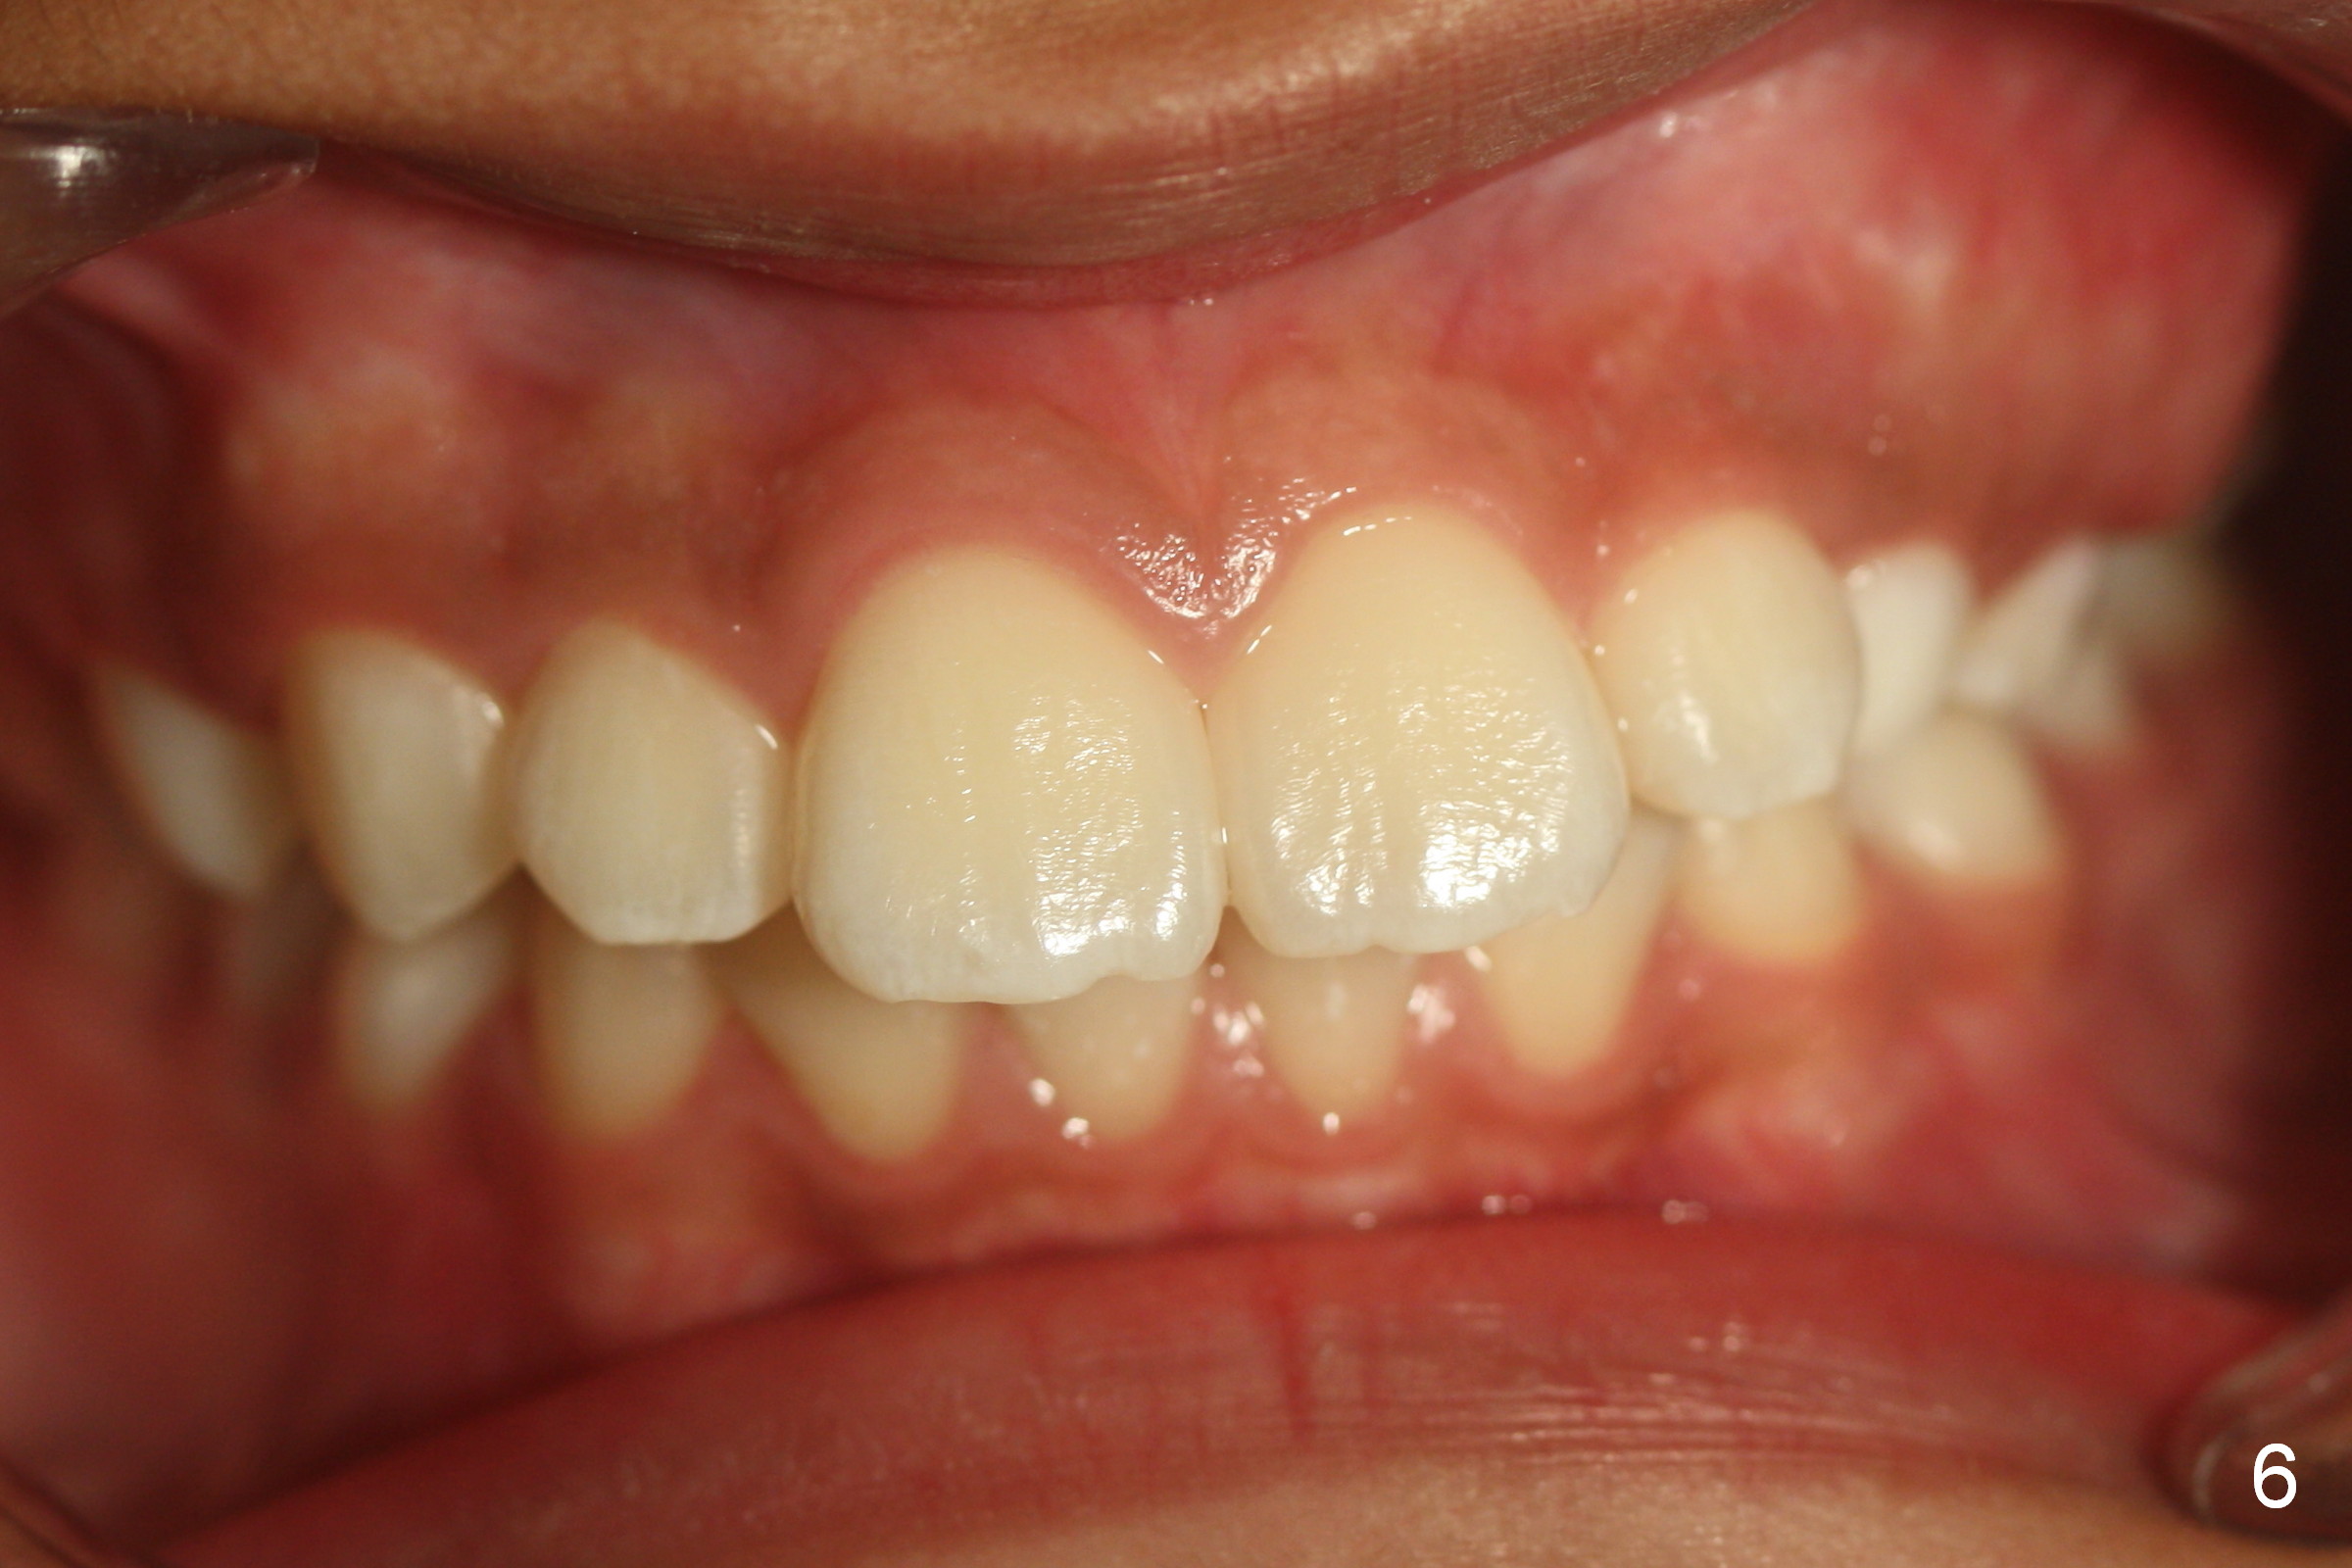

A 11-year-old boy has history of asthma. His father has sleep apnea with similar Class II malocclusion. Pan was taken for the boy 3 years ago (Fig.1). His mother wants to have orthodontic treatment as early as possible, because of protrusive upper anterior teeth. The dentition is permanent except the upper left canine and 1st molar (Fig.7,10,12,13 C, D). It appears that there is bilateral Class II occlusion at canine by half a tooth (Fig.9-12). The malocclusion and facial profile can be easily corrected with extraction of the upper 1st bicuspids.

On the other hand, orthodontics without extraction may improve the mandibular position by using Class II retraction. The tongue may be advanced with increased pharyngeal space. Sleep apnea possibility may be reduced. What is your choice of treatment?